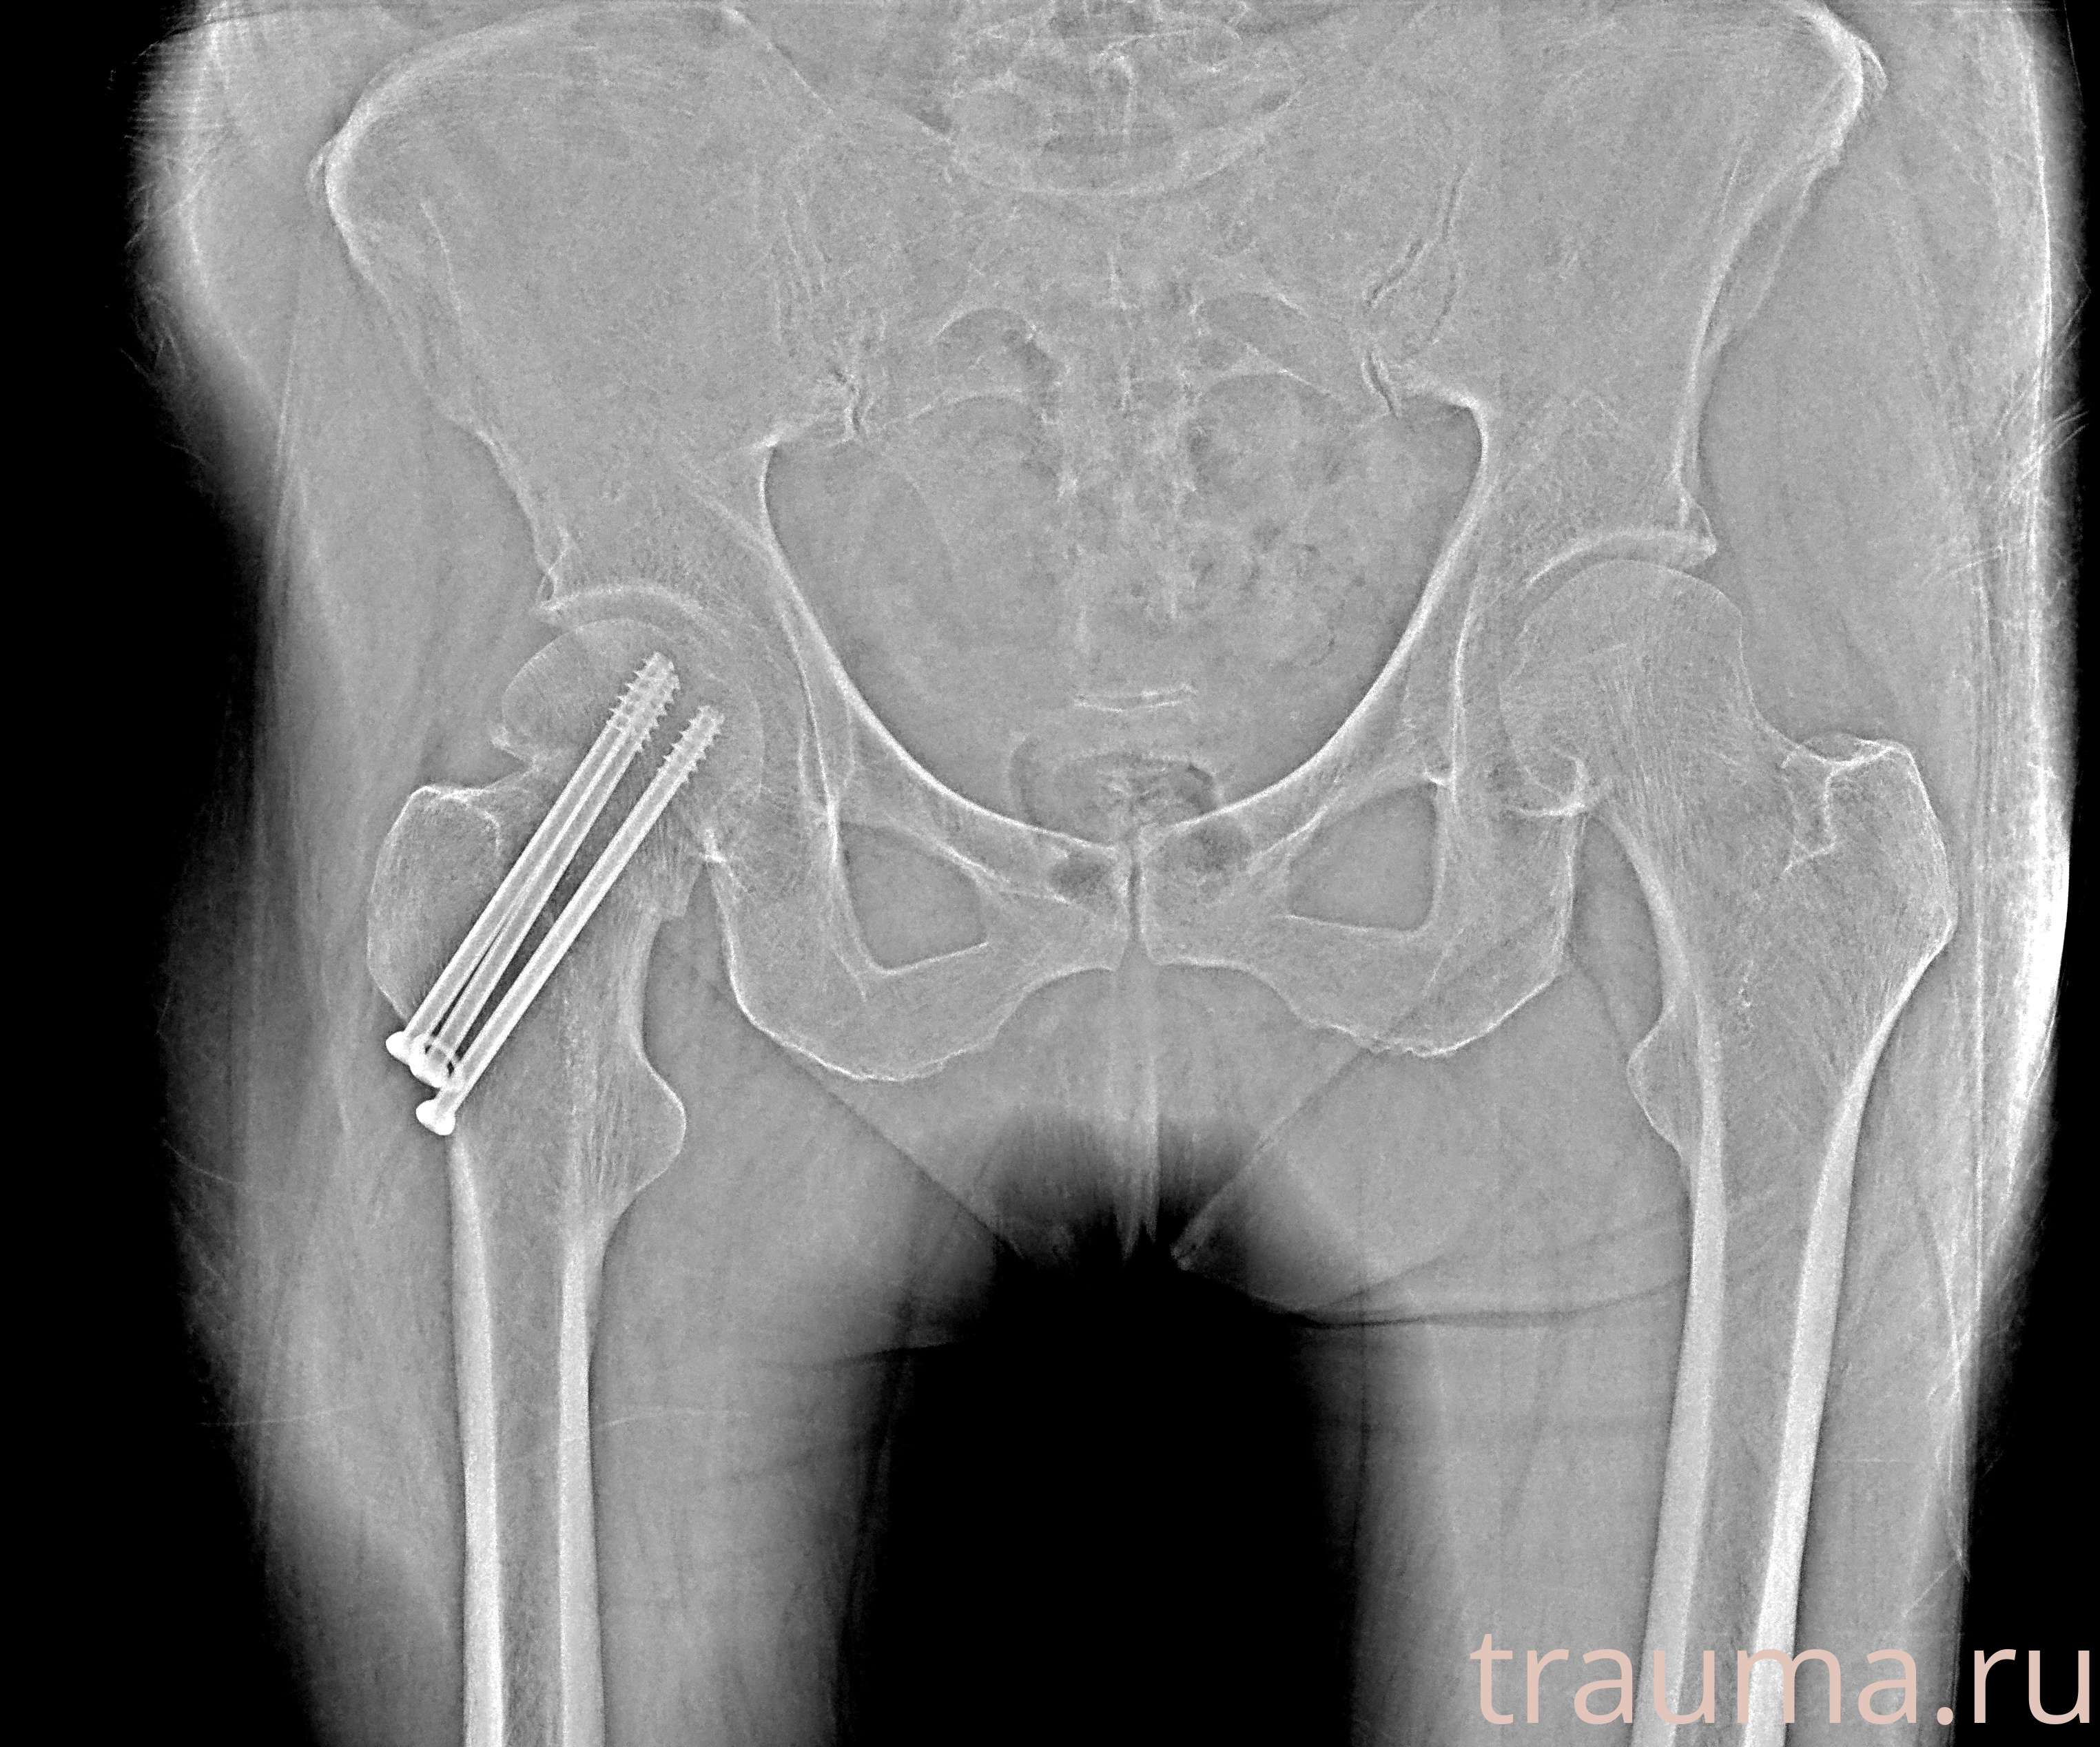

Рентгенограммы

Рентген на дому: по вашему адресу приезжает врач-рентгенолог, травматолог-ортопед с мобильным рентгеновским аппаратом, проводит диагностику травмы или заболевания, делает необходимые рентгенограммы, дает рекомендации по дальнейшему лечению. Получить качественные снимки в домашних условиях возможно благодаря уникальной методике, разработанной МосРентген Центром для института  Склифосовского